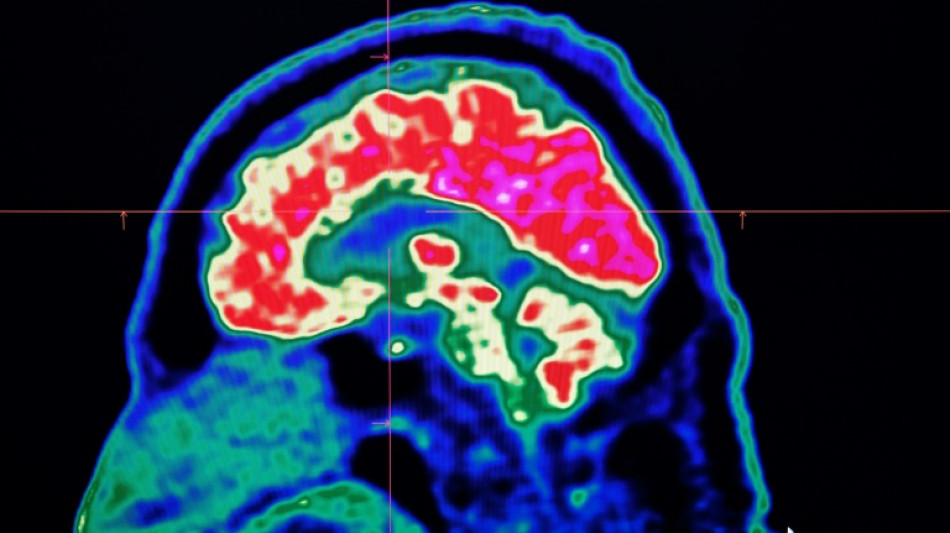

What are all these microplastics doing to our brains? / Photo: Fred TANNEAU - AFP/File

Tiny shards of plastic called microplastics have been detected accumulating in human brains, but there is not yet enough evidence to say whether this is doing us harm, experts have said.

These mostly invisible pieces of plastic have been found everywhere from the top of mountains to the bottom of oceans, in the air we breathe and the food we eat. They have also been discovered riddled throughout human bodies, inside lungs, hearts, placentas and even crossing the blood-brain barrier.

The most prominent study looking at microplastics in brains was published in the journal Nature Medicine in February.

The scientists tested brain tissue from 28 people who died in 2016 and 24 who died last year in the US state of New Mexico, finding that the amount of microplastics in the samples increased over time.

The study made headlines around the world when the lead researcher, US toxicologist Matthew Campen, told the media that they detected the equivalent of a plastic spoon's worth of microplastics in the brains.

Campen also told Nature that he estimated the researchers could isolate around 10 grammes of plastic from a donated human brain -- comparing that amount to an unused crayon.